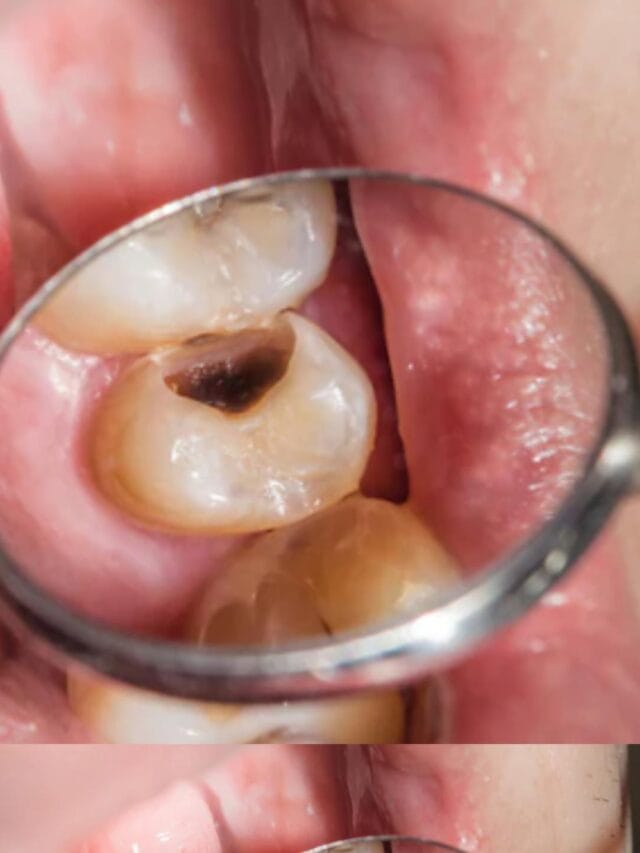

दांतों के सड़ने से ऐसे बचाएं | Tooth Cavity Remedies

Tooth Cavity Home Remedies: दांतों की कैविटी एक आम समस्या है। दांतों की कैविटी के कारण दांत सड़ने लगता है, टूट जाता है और दर्द का कारण भी बनता है।…